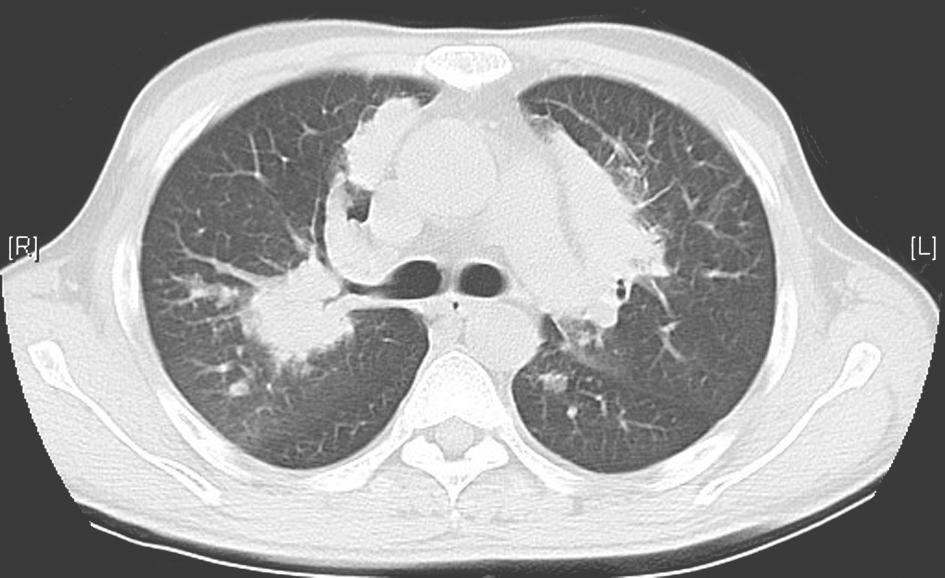

【临床转归】

行抗结核治疗1年后,复查胸部CT示双肺病灶明显吸收(图7)。

图7 抗结核治疗1年后胸部CT表现